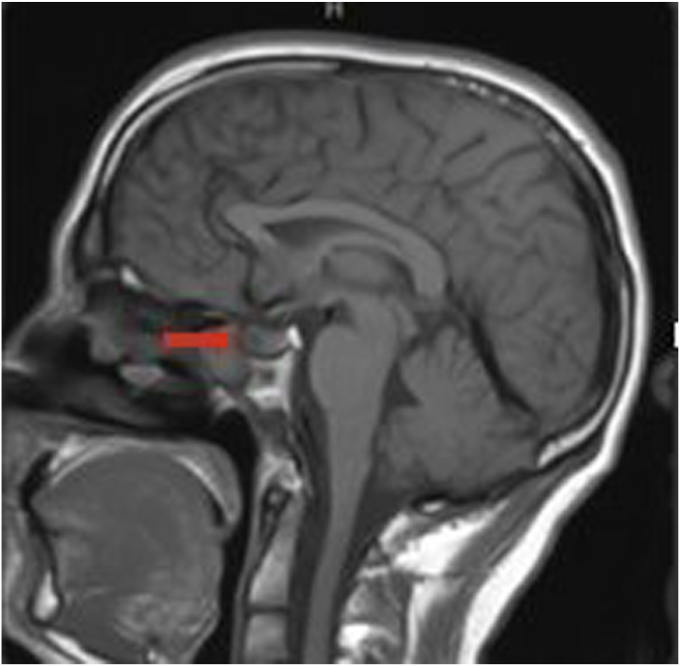

The patient was a 31-year-old man with history of CF who was referred to endocrinology clinic for the evaluation of hypogonadism. Serum testing revealed a total testosterone of 175 ng/mL (296-1377), luteinizing hormone 2.8 mIU/mL (1.2-8.6), and a prolactin of 341 ng/mL (3-13). A brain magnetic resonance imaging was obtained, which revealed a 1 cm hypoenhancing left sellar lesion. He was started on cabergoline. His testosterone increased to 707 ng/dL after a year on cabergoline treatment. His prolactin decreased to 12 ng/mL after a year of treatment. The pituitary adenoma decreased 50% in size 2 years after cabergoline was initiated.